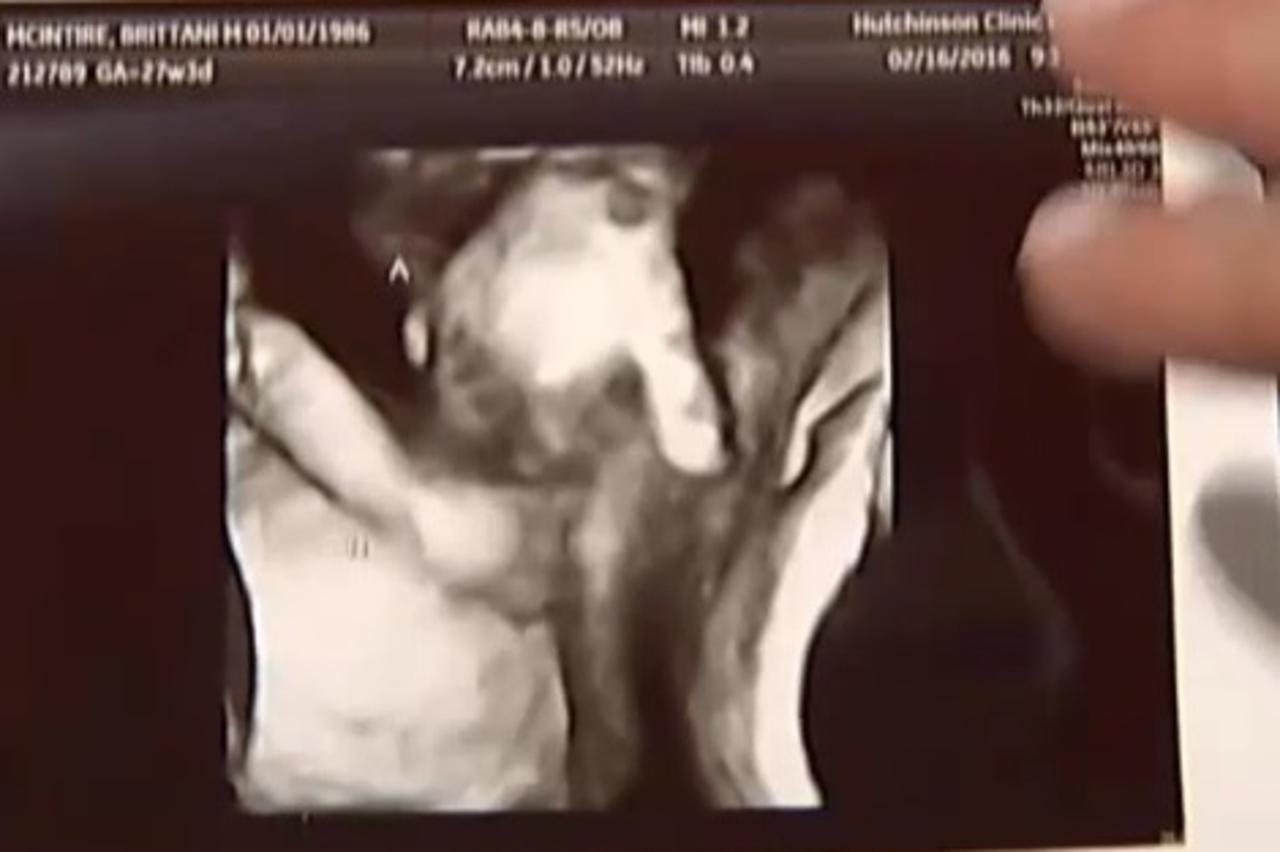

56 Mala utjeha Nakon što je saznala da joj jedno dijete umire, vidjela ovu sliku ultrazvuka Brittani i njezin suprug Ian nisu planirali imati još djece, a kamoli blizance